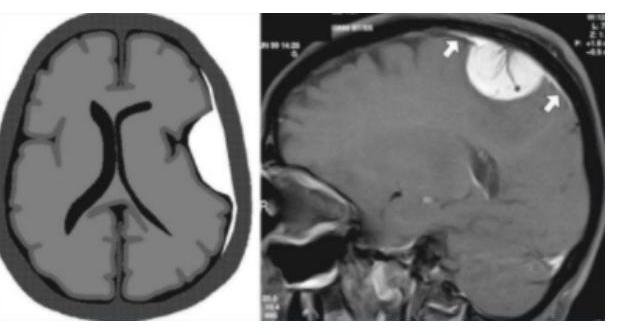

# **TUMORES DEL SNC** ## **DEFINICIÓN** Los tumores cerebrales representan un grupo grande y heterogéneo de neoplasias cuyo factor común es un desequilibrio que se produce en relación con la proliferación/muerte celular debido a la acumulación de células provocada por mecanismos genéticos o epigenéticos. ## **EPIDEMIOLOGÍA** - Los meningiomas son los tumores primarios más frecuentes. - En cuanto a tumores generales, las **METÁSTASIS** son los tumores cerebrales más frecuentes. - El cáncer de pulmón de células pequeñas es la metástasis a cerebro más frecuente. - Las neoplasias cerebrales representan 15-20% de los tumores en infancia y adolescencia. - Pediátricos: **FOSA CRANEAL POSTERIOR**, **TALLO** y **CEREBELO** (60% de los tumores). - Adultos: **SUPRATENTORIAL**. - El tamaño de la lesión **NO SE RELACIONA CON EL PRONÓSTICO**. - El Glioblastoma Multiforme es el tumor primario más común en el adulto (**MAL PRONÓSTICO**). ## **FACTORES DE RIESGO** - Genéticos (NFM 1 y 2, Esclerosis Tuberosa, Ataxia Telangiectasia, Sx Von Hippel-Lindau, Sx Sturge-Weber) - Inmunológicos - Radiación **IONIZANTE** (Radiografías, TAC, Hemodinamia) - Exposición a hidrocarburos aromáticos - Neurofibromatosis ## **CLÍNICA** - **CEFALEA** (es el síntoma más común). - Característica: Que lo despierta en la noche. - Náuseas/vómitos - Focalidad neurológica - Alteración de la personalidad - Nistagmo - **HIPERTENSIÓN INTRACRANEAL**: **CEFALEA MATUTINA** + **NÁUSEA** + **VÓMITO**. - **SÍNDROME CEREBELOSO**: **VERMIANO** + **ATAXIA TRONCAL** o de la **MARCHA** + **DISMETRÍA** + **DISARTRIA** + **ROTS** pendulares. ## **SÍNDROME DE HIPERTENSIÓN INTRACRANEAL CRÓNICO**: - Puede ser por hidrocefalia, tumores o infección. - Síntomas de un solo lado: Pensar en **CORTEZA CEREBRAL**. - Síntomas bilaterales y pares craneales en contralateral: **TALLO CEREBRAL**. - Síntomas de marcha y nistagmus del mismo lado de la lesión del **CEREBELO**. ## **DATOS DE ALARMA**: **CEFALEA CRÓNICA Y PROGRESIVA**, **VÓMITO RECURRENTE**, **ALTERACIONES VISUALES**, **DISFUNCIÓN ENDOCRINA**, **REGRESIÓN DE HITOS DEL DESARROLLO**, **ALTERACIÓN EXAMEN NEUROLÓGICO**. - **PAPILEDEMA** + **FONTANELA TENSA** + **VÓMITO** + **OJOS EN SOL NACIENTE** (no se pueden levantar). ## **TRIADA DE CUSHING** (**HIPERTENSIÓN INTRACRANEANA**) Sucede cuando el efecto de masa aumenta la PIC: **HIPERTENSIÓN** + **BRADICARDIA** + **ALTERACIONES RESPIRATORIAS**. # **DIAGNÓSTICO** ## 1ra elección: **EXPLORACIÓN NEUROLÓGICA** Debe realizarse un examen neurológico exhaustivo ya que en más del \mathbf{95 \%} de los casos se encuentra alguna alteración neurológica añadida a los síntomas que motivaron la consulta. ## **GOLD STANDARD**: **RMN CON GADOLINIO** Ante la sospecha de tumor cerebral, el estudio de imagen más importante siempre será **RMN CON GADOLINIO**. ## **TAC** En su modalidad simple o contrastada es una alternativa útil cuando no se cuenta con RMN y cuando es indispensable descartar **HIDROCEFALIA** asociada.  # **MANEJO INICIAL** - Posición neutra. - Elevación 15-30°. - Descompresión abdominal con SNG. - Si hay falla respiratoria, **INTUBACIÓN ENDOTRAQUEAL** de secuencia rápida. ## **ESTADO EPILÉPTICO** - **MIDAZOLAM** Fenitoína puede recomendarse en menores de 6 años de forma empírica para evitar la recurrencia. No se recomienda el uso de antiepilépticos profilácticos. ## **MANEJO ANTIEDEMA** ## 1ra e: **DEXAMETASONA IV** - Dosis de 1 mg/kg como dosis de carga y posteriormente 1-1.5 mg/kg dividido en 4 dosis. # **ASTROCITOMA** - Es la neoplasia cerebral más frecuente en **NIÑOS**. A nivel histopatológico aparecen **FIBRAS DE ROSENTHAL** en la tinción hematoxilina-eosina. **LOCALIZACIÓN**: **INFRATENTORIAL** (43%). ## **CARACTERÍSTICAS** - Causan **CRISIS EPILÉPTICAS**. - No captan **CONTRASTE**. - Aparecen en **LÓBULO FRONTAL** y **TEMPORAL**.  | GRADO OMS | GRADO | TRATAMIENTO | | :--: | :-- | :-- | | Grado I | Bajo Grado | **CIRUGÍA** | | Grado II | Bajo Grado | **CIRUGÍA**. Radioterapia si no es resecable. Quimioterapia en recurrencias. | | Grado III | **ANAPLASIA** y **ACTIVIDAD MITÓTICA** | **CIRUGÍA** + **RT** + **QT**. | | Grado IV | **PROLIFERACIÓN MICROVASCULAR** y **NECROSIS** | | ## **OLIGODENDROGLIOMA** ## **CARACTERÍSTICAS** Es el tumor más **EPILEPTÓGENO**. **LÓBULO FRONTAL**. Histopatología: Aspecto de **HUEVO FRITO**. **TRATAMIENTO**: - **CIRUGÍA** + **QUIMIOTERAPIA**. ## **EPENDIMOMA** ## **CARACTERÍSTICAS** Afecta principalmente la **MÉDULA ESPINAL** y el suelo del \(4^{\circ}\) ventrículo. Es común en **NIÑOS**. **TRATAMIENTO**: - **CIRUGÍA** + **RADIOTERAPIA**.  ## **MEDULOBLASTOMA** ## **CARACTERÍSTICAS** - Es la neoplasia más frecuente en **MENORES DE 5 AÑOS**. - Asociación con Síndromes de **LI-FRAUMENI** y **TURCOT**. - Localizado en el techo del \(4^{\circ}\) ventrículo. Histopatología: **ROSETA DE HOMER-WRIGHT**. ## **TRATAMIENTO** - **CIRUGÍA** + **QUIMIOTERAPIA** + **RADIOTERAPIA**. ## **MENINGIOMA** - \(2^{\circ}\) neoplasia más frecuente en el adulto (después del **GLIOMA**). - Típico en **MUJERES** de \(5^{a}\) y \(6^{a}\) década. - Se asocia a **CA DE MAMA** y **TVP**. ## RMN: **COLA DURAL**. ## **TRATAMIENTO** - **CIRUGÍA**. ## **GERMINOMA** - Es el tumor **PINEAL** más frecuente. - Se acompaña de **DIABETES INSÍPIDA** / **PUBERTAD PRECOZ**. - Es un tumor **INVASOR** y causa **HIDROCEFALIA**. ## **TRATAMIENTO** - **RADIOTERAPIA**.  | TUMOR | LOCALIZACIÓN | DIAGNÓSTICO | DATOS | | :--: | :--: | :--: | :--: | | ASTROCITOMA | **INFRATENTORIAL** (43%). **PISO DEL \(4^{\circ}\) VENTRÍCULO**. | RMN: **REALCE EN ANILLO**. | Tumor cerebral más frecuente en **PEDIATRÍA** (<18 años). | | MEDULOBLASTOMA | Localizado en el techo del \(4^{\circ}\) ventrículo. | **PUNCIÓN LUMBAR**: Se buscan células y marcadores específicos preoperatorios. | Tumor más frecuente en **<4 AÑOS**. Tumor embrionario altamente **MALIGNO** con tendencia a la **DISEMINACIÓN LEPTOMENÍNGEA**. Asociación con Síndromes de **LI-FRAUMENI** y **TURCOT**. | | OLIGODENDROGLIOMA | **LÓBULO FRONTAL**. | Histopatología: Aspecto de **HUEVO FRITO**. | Es el tumor más **EPILEPTÓGENO**. | | EPENDIMOMA | **MÉDULA ESPINAL** y el suelo del \(4^{\circ}\) ventrículo. Se origina de células ependimarias del sistema ventricular y canal central de médula. | **ROSETAS PERIVASCULARES**. | Lesión **FOSA CRANEAL POSTERIOR**. **EDAD MEDIA**: 5.6 **AÑOS**. | | MENINGIOMA | Tumor localizado en las **MENINGES**. | RMN: **COLA DURAL**. | \(2^{\circ}\) neoplasia más frecuente en el adulto (después del **GLIOMA**). Es el **TUMOR NO MALIGNO** más frecuente en el adulto. Se asocia a **CA DE MAMA** y **TVP**. | | GERMINOMA | **GLÁNDULA PINEAL**. Tumor **INVASOR** y causa **HIDROCEFALIA**. | Asociado a **DIABETES INSÍPIDA** / **PUBERTAD PRECOZ**. | Es el tumor **PINEAL** más frecuente. | # **SÍNTOMAS DE AUMENTO DE PRESIÓN INTRACRANEANA**: 1. **VÓMITOS** (69%). 2. **CEFALEA** (53%). 3. **ATAXIA** (27%). 4. **LATERALIZACIÓN DE CABEZA** (8%). 5. **CONVULSIONES** (6%).

# TUMORES DEL SNC ## DEFINICIÓN Los tumores cerebrales representan un grupo grande y heterogéneo de neoplasias cuyo factor común es un desequilibrio que se produce en relación a la proliferación/muerte celular a factor de la acumulación de células, provocado por mecanismos genéticos o epigenéticos. ## EPIDEMIOLOGÍA - Los meningiomas son los tumores primarios más frecuentes. - En cuanto a tumores generales, las METÁSTASIS son los tumores cerebrales más frecuentes. - El cáncer de pulmón de células pequeñas es la metástasis a cerebro más frecuente. - Las neoplasias cerebrales representan 15-20 % de los tumores en infancia y adolescencia. - Pediátricos FOSA CRANEAL POSTERIOR, TALLO y CEREBELO (60% de los tumores) - Adultos SUPRATENTORIAL. - El tamaño de la lesión NO SE RELACIONA CON EL PRONÓSTICO. - El Glioblastoma Multiforme es el tumor primario más común en el adulto (mal pronóstico) ## FACTORES DE RIESGO - Genéticos (NFM 1 y 2, Esclerosis Tuberosa, Ataxia Telangiectasia, Sx Von-Hipel-Lindau, Sx Sturge-Weber) - Inmunológicos - Radiación IONIZANTE (Radiografías, TAC, Hemodinamia) - Exposición a hidrocarburos aromáticos - Neurofibromatosis CLÍNICA - CEFALEA (es el síntoma más común) - Característica: que lo despierta en la noche - Náuseas/Vómitos - Focalidad Neurológica - Alteración en la personalidad - Nistagmo - Hipertensión Intracraneal: CEFALEA MATUTINA + NÁUSEA + VÓMITO - Síndrome Cerebeloso: Vermiano + Ataxia Troncal o de la Marcha + Dismetría + Disartria + ROTS pendulares. ## SÍNDROME DE HIPERTENSIÓN INTRACRANEAL CRÓNICO: - Puede ser por hidrocefalia, tumores o infección - Síntomas de un solo lado: Pensar en corteza cerebral - Síntomas bilaterales y pares craneales en contralateral: Tallo cerebral - Síntomas de marcha y nistagmus del mismo lado de la lesión del Cerebelo ## DATOS DE ALARMA: cefalea crónica y progresiva, vómito recurrente, alteraciones visuales, disfunción endócrina, regresión de hitos del desarrollo, alteración examen neurológico. - Papiledema + Fontanela Tensa + Vómito + Ojos en sol naciente (no se pueden levantar) TRIADA DE CUSHING (Hipertensión Intracraneana) Sucede cuando el efecto de masa aumenta la PIC Hipertensión + Bradicardia + Alteraciones Respiratorias # DIAGNÓSTICO ## 1ra elección: EXPLORACIÓN NEUROLÓGICA Debe realizarse un examen neurológico exhaustivo ya que en más del \mathbf{9 5 %} de los casos se va a encontrar alguna alteración neurológica agregada a los síntomas que motivaron la consulta. ## GOLD STANDARD: RMN CON GADOLINEO Ante la sospecha de tumor cerebral el estudio de imagen más importante siempre será RMN CON GADOLINIO. ## TAC En su modalidad simple o contrastada es una alternativa útil cuando no se cuenta con RMN y cuando es indispensable descartar hidrocefalia asociada  # MANEJO INICIAL - Posición neutra - Elevación 15-30 - Descompresión abdominal con SNG - Si hay falla respiratoria Intubación Endotraqueal de secuencia rápida ## ESTADO EPILÉPTICO - MIDAZOLAM Fenitoína puede recomendarse en menores de 6 años de forma empírica para evitar la recurrencia. No se recomienda el uso de antiepilépticos profilácticos. ## MANEJO ANTIEDEMA ## 1rae: DEXAMETASONA IV - Dosis de 1 mg / kg como dosis de carga y posteriormente 1 - 1.5 dividido en 4 dosis. # ASTROCITOMA ## - Es la neoplasia cerebral más frecuente en niños. A nivel histopatológico aparecen Fibras de Rosenthal en la tinción hematoxilina-eosina. LOCALIZACIÓN: INFRATENTORIAL (43%) ## CARACTERÍSTICAS - Causan crisis epilépticas - No captan contraste - Aparecen en Lóbulo frontal y temporal  ## RMN - Realce en Anillo | GRADO OMS | GRADO | TRATAMIENTO | | :--: | :-- | :-- | | Grado I | Bajo Grado | Cirugía | | Grado II | Bajo Grado | Cirugía Radioterapia si no es resecable Quimioterapia en recurrencias | | Grado III | Anaplasia y Actividad Mitótica | Cirugía + RT + QT Cirugía + RT + QT | | Grado IV | Proliferación microvascular y necrosis | | ## OLIGODENDROGLIOMA ## CARACTERÍSTICAS Es el tumor más epileptógeno Lóbulo frontal Histopatología: Aspecto de Huevo Frito Tratamiento: - Cirugía + Quimioterapia ## EPENDIMOMA ## CARACTERÍSTICAS Afecta principalmente la médula espinal y el suelo del 4^{\circ} ventrículo Es común en niños. Tratamiento: - Cirugía + Radioterapia  ## MEDULOBLASTOMA ## CARACTERÍSTICAS - Es la neoplasia más frecuente en MENORES 5 años. - Asociación con Síndromes de Li-Fraumeni y Turcot. - Localizado en el techo del 40 ventrículos. Histopatología: Roseta de Homer-Wright ## TRATAMIENTO - Cirugía + Quimioterapia + Radioterapia ## MENINGIOMA - 20 neoplasia más frecuente en el adulto (después del Glioma) - Típico en mujeres de 5o y 6o década - Se asocia a Ca de Mama y TVP ## RMN: Cola Dural - ## TRATAMIENTO - Cirugía ## GERMINOMA - Es el tumor PINEAL más frecuente - Se acomaña a diabetes insípida/pubertad precoz - Es un tumor invasor y causa hidrocefalia ## TRATAMIENTO - Radioterapia  | TUMOR | LOCALIZACIÓN | DIAGNÓSTICO | DATOS | | :--: | :--: | :--: | :--: | | ASTROCITOMA | INFRATENTORIAL (43 %) PISO DEL 4^{\circ} VENTRICULO | RMN: Realce en Anillo | Tumor cerebral más frecuente en pediatría ( <18 años) | | MEDULOBLASTOMA | Localizado en el techo del 4^{\circ} ventrículos. | PUNCIÓN LUMBAR: Se buscan células y marcadores específicos preoperatorios. | Tumor más frecuente en <4 años Tumor embrionario altamente maligno con tendencia a la diseminación leptomeníngea Asociación con Síndromes de Li- Fraumeni y Turcot. | | OLIGODENDROGLIOMA | Lóbulo frontal | Histopatología: Aspecto de Huevo Frito | Es el tumor más epileptógeno | | EPENDIMOMA | Médula espinal y el suelo del 4^{\circ} ventrículo Se origina de células ependimarias del sistema ventricular y canal central de médula | Rosetas perivasculares | Lesión FOSA CRANEAL POSTERIOR EDAD MEDIA: 5.6 AÑOS | | MENINGIOMA | Tumor localizado en las meninges. | RMN: Cola Dural | 2^{\circ} neoplasia más frecuente en el adulto (después del Glioma) Es el TUMOR NO MALIGNO más frecuente en el adulto. Se asocia a Ca de Mama y TVP | | GERMINOMA | Glándula Pineal Tumor invasor y causa hidrocefalia | Asociado a Diabetes Insípida/pubertad precoz | Es el tumor PINEAL más frecuente. | # SÍNTOMAS DE AUMENTO DE PRESIÓN INTRACRANEANA: ## 1. Vómitos 69% 2. Cefalea 53 % 3. Ataxia 27 % 4. Lateralización de Cabeza 8 5. Convulsiones 6 %